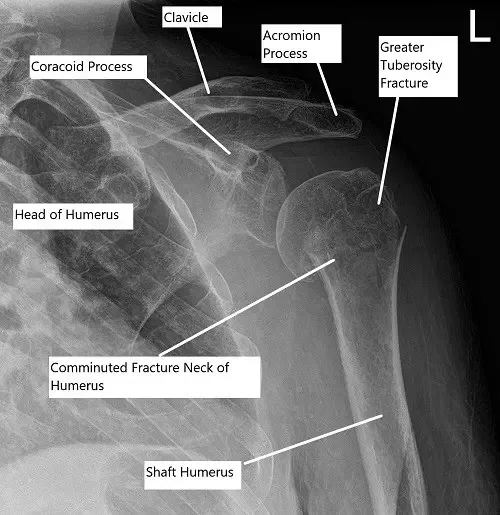

Radiografía preoperatoria del hombro que mostró una fractura en tres partes del húmero proximal

Los estudios radiológicos en forma de radiografía revelaron una fractura conminuta de la cabeza y el cuello del húmer. Una tomografía computarizada del hombro izquierdo reveló una fractura humeral proximal conminuta que está impactada y un componente fractural ligeramente angulado en el cuello quirúrgico, un fragmento de fractura ligeramente desplazado en la mayor tuberosidad y una sutil fractura no desplazada en la menor tuberosidad.